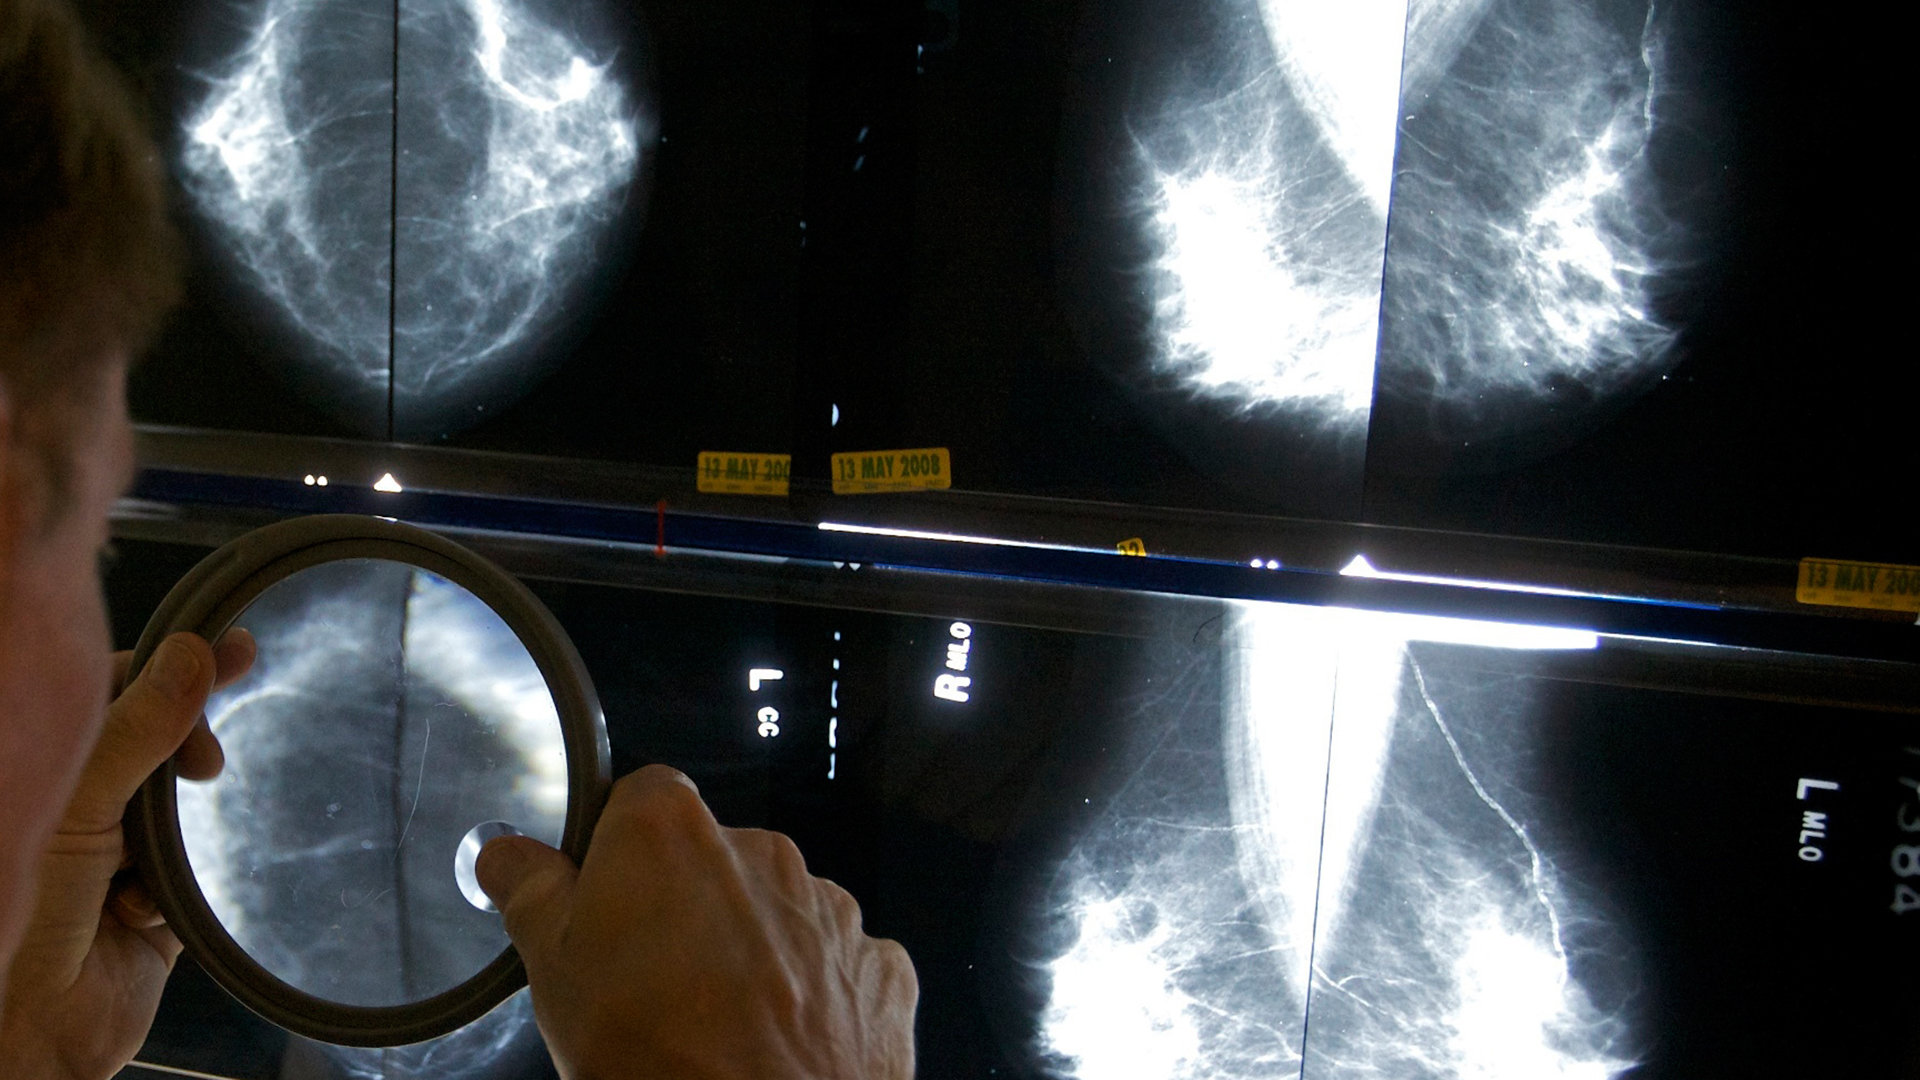

Ο Ηλίας Αθανασιάδης, ογκολόγος – παθολόγος, επικεφαλής της Ογκολογικής Κλινικής του Νοσοκομείου «Μητέρα», δεν κρύβει την ικανοποίησή του για το γεγονός ότι στον πόλεμο με τον καρκίνο του μαστού η Ογκολογία σημειώνει εντυπωσιακές νίκες, καθώς και την αισιοδοξία του για το μέλλον: «Τις τελευταίες τρεις δεκαετίες οι θάνατοι σταθερά μειώνονται και “κατακτάται” ολοένα και μεγαλύτερη χρονιότητα. Πέρα από την επιστημονική πρόοδο που μας άνοιξε τον δρόμο για καινούργιες, πιο αποτελεσματικές, θεραπευτικές προσεγγίσεις, συνέβαλαν κι άλλοι παράγοντες σ’ αυτό: το γεγονός ότι σε μεγάλο ποσοστό οι γυναίκες προσέχουν πιο πολύ τον εαυτό τους, γυμνάζονται, σταμάτησαν να παίρνουν οιστρογόνα ως θεραπεία ορμονικής υποκατάστασης, μεταξύ άλλων», λέει στην «Κ». Ο κ. Αθανασιάδης θεωρεί θετική εξέλιξη την επέκταση του προγράμματος προσυμπτωματικού ελέγχου, «Φώφη Γεννηματά», στις γυναίκες 45-74 ετών (από 50-69 ετών) που ανακοινώθηκε χθες. «Η μαστογραφία αποτελεί πολύτιμο εργαλείο πρόληψης και πρώιμης διάγνωσης. Πέρα όμως από το προγραμματισμένο μαζικό screening για υγιείς γυναίκες, υπάρχει και το εξατομικευμένο, για τις άνω των 40, με βάση τον κίνδυνο που διατρέχουν λόγω κληρονομικότητας ή των γονιδίων BRCA1 και BRCA2», εξηγεί.

Τρίτον: υπάρχει η τεχνητή νοημοσύνη. Σουηδική έρευνα που δημοσιεύτηκε πρόσφατα στο Lancet Oncology καταδεικνύει ότι η AI μπορεί να «διαβάσει» μαστογραφίες και υπερηχογραφήματα κατά τον προσυμπτωματικό έλεγχο, εντοπίζοντας με μεγάλη ακρίβεια και αξιοπιστία αλλοιώσεις, αλλά και ξεχωρίζοντας ποια από τα ευρήματα είναι καλοήθη και ποια κακοήθη. Στη δοκιμή συμμετείχαν περισσότερες από 80.000 γυναίκες.